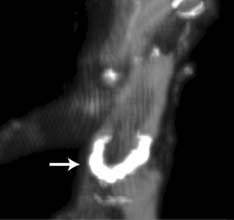

While atherosclerosis has been observed before in ancient Egyptians, this study found it to be more prevalent than previously thought. The interdisciplinary team performed whole body computerized tomography (CT) scans on 52 ancient Egyptian mummies to determine if atherosclerosis was present. Of the 44 with identifiable arteries or hearts, nearly half (45 percent) had calcifications either in the wall of an artery or along the course of an artery that are diagnostic of or highly suggestive of atherosclerosis. “Commonly, we think of coronary artery or heart disease as a consequence of modern lifestyles, mainly because it has increased in developing countries as they become more westernized,” said Gregory S. Thomas, M.D., MPH, clinical professor and director of nuclear cardiology education, University of California, Irvine and the study’s co-principal investigator.

“These data point to a missing link in our understanding of heart disease, and we may not be so different from our ancient ancestors.” Most of the atherosclerosis was found in the large arteries of the body, including the aorta in the abdomen. However, key smaller arteries were also involved. About 7 percent of the mummies had obstructions in the heart arteries, and 14 percent had blockages in the arteries to the brain, the carotid arteries, which is a leading cause of stroke in the present day. Researchers also found that, similar to now, advancing age was highly predictive of the presence and severity of atherosclerosis.

Thomas explains that the calcific atherosclerosis seen with CT scanning looks just like the atherosclerosis of today and appears in the same locations. While researchers could not determine the exact cause of death in these mummies, symptoms consistent with cardiac chest pain had been described in ancient Egyptian scrolls. In order to understand the lifestyles of ancient Egypt’s elite, the team of researchers worked with Egyptologists to review risk factors that might affect the health of the heart and arteries.